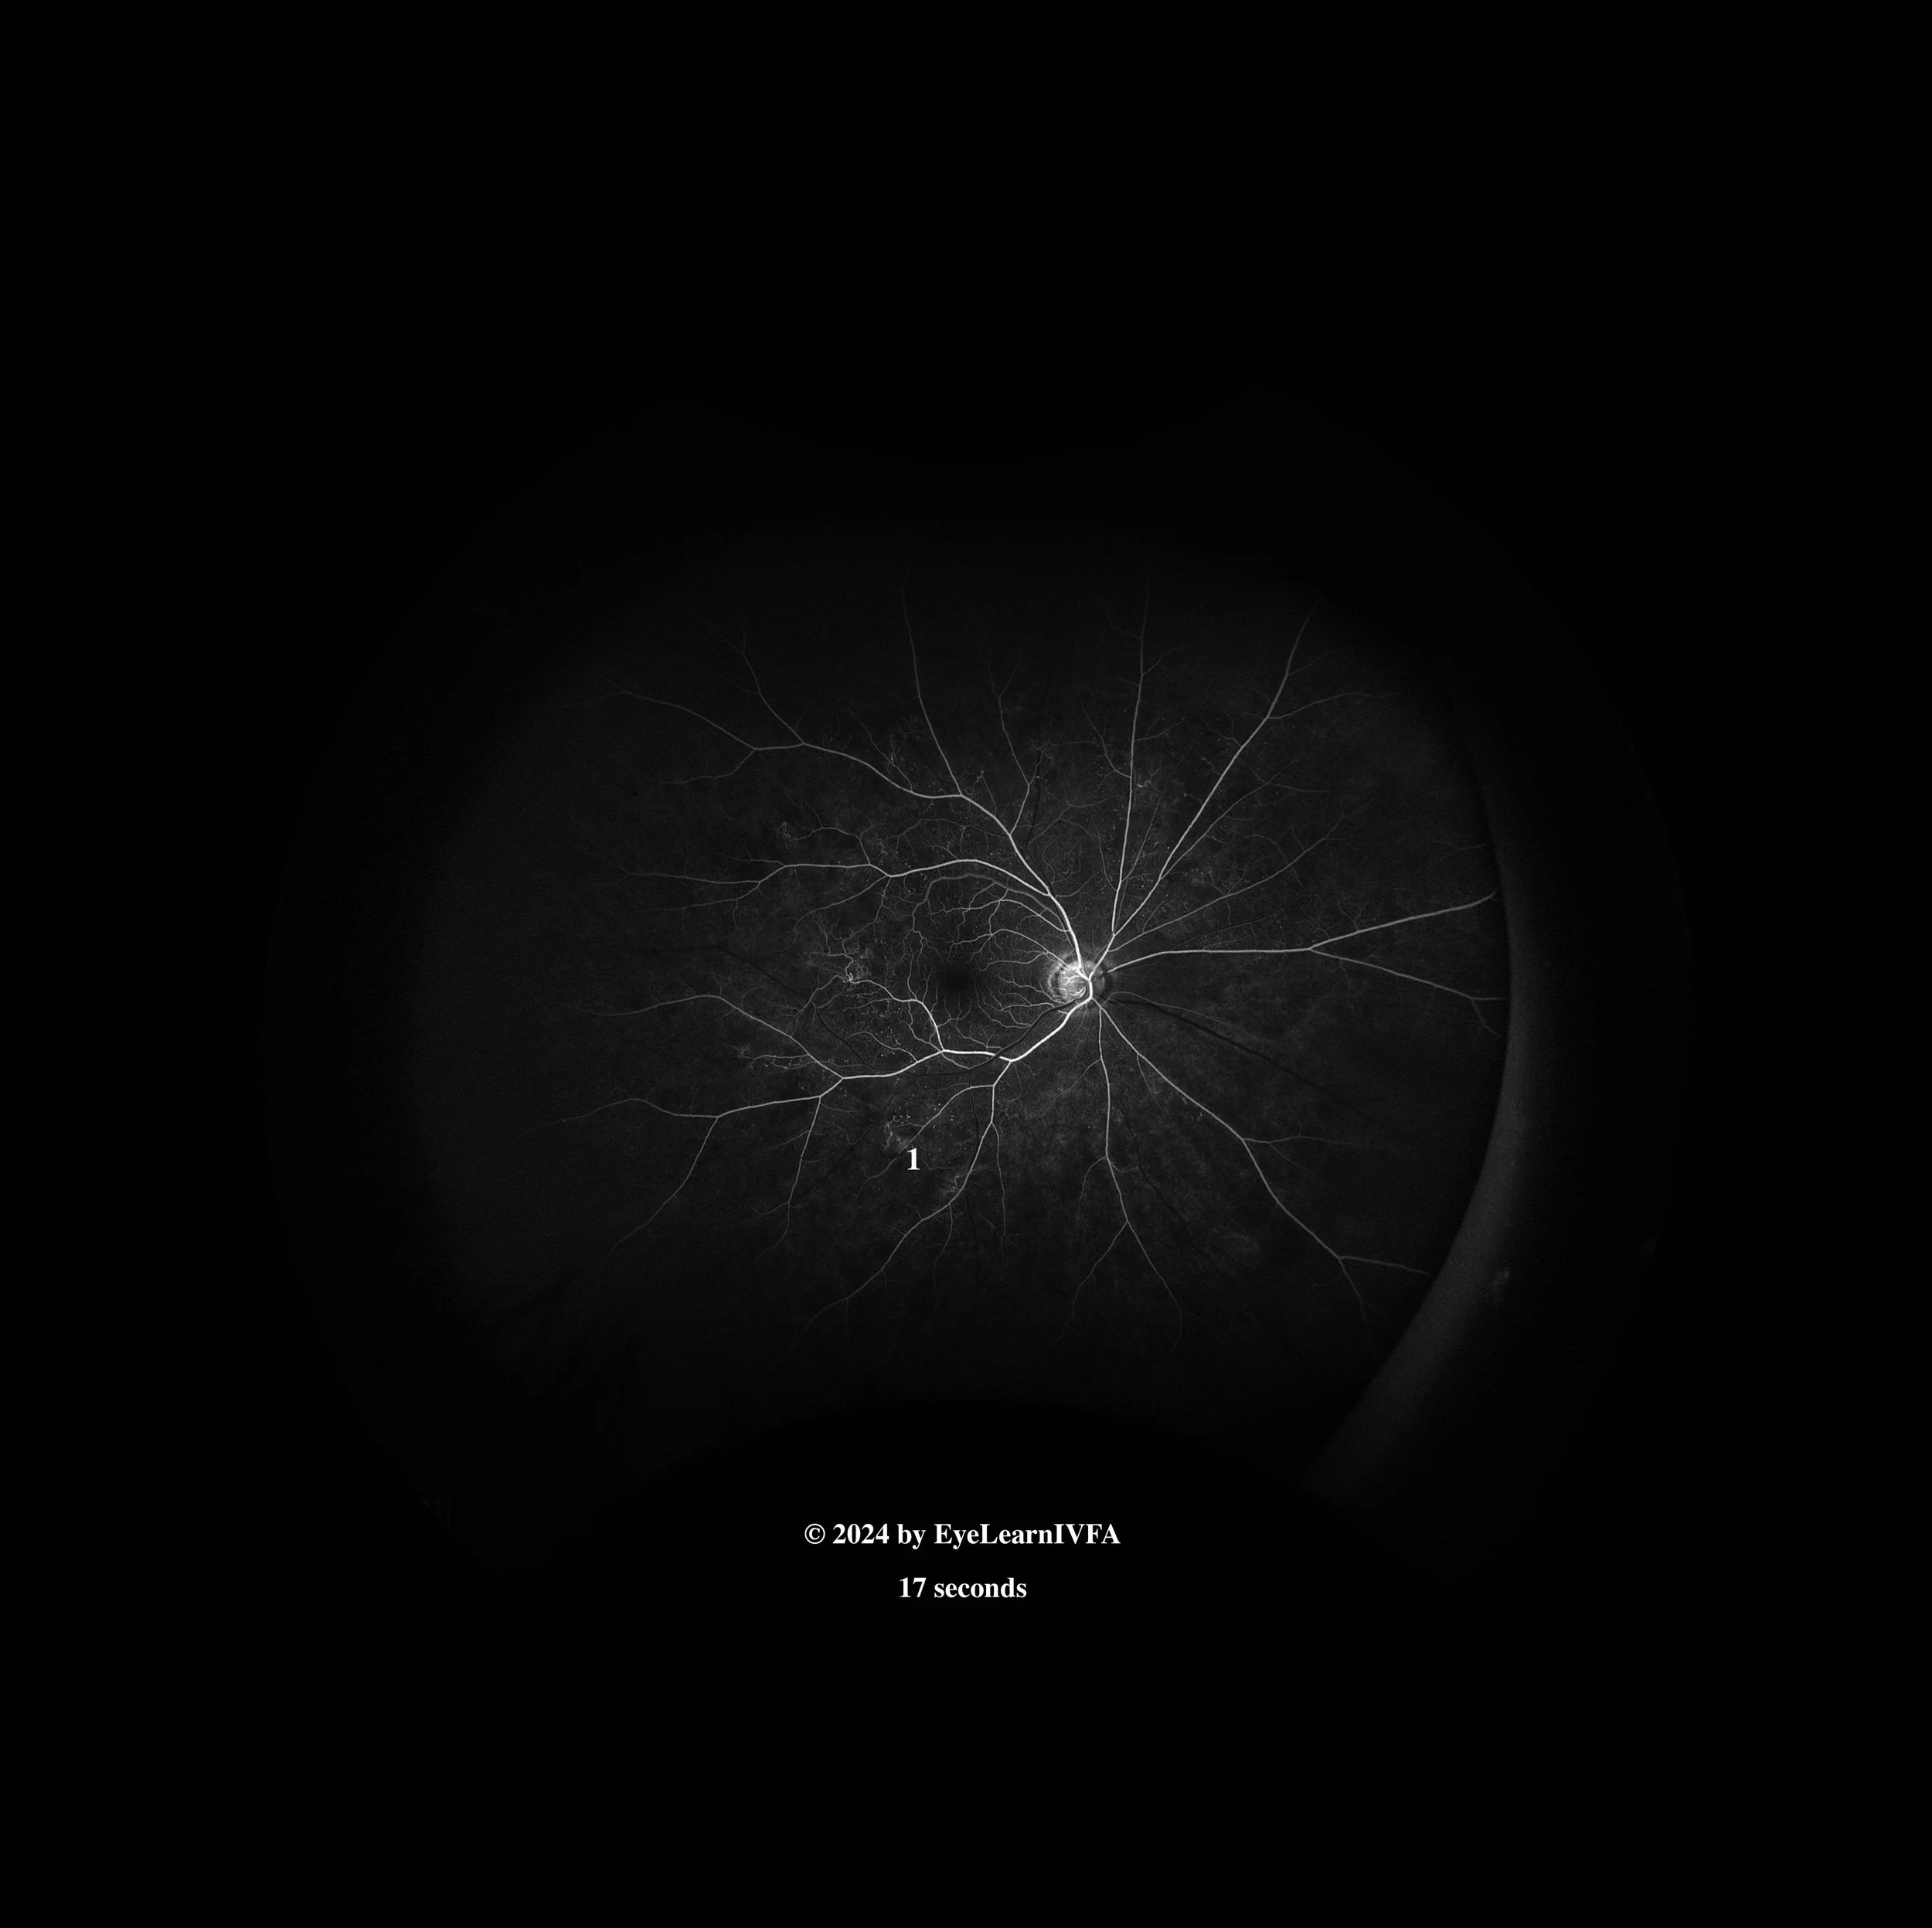

• IVFA at 17 seconds

Arterial phase

Key features include:

• Several hyperfluorescent dots concentrated around the vasculature representing microaneurysms (1)